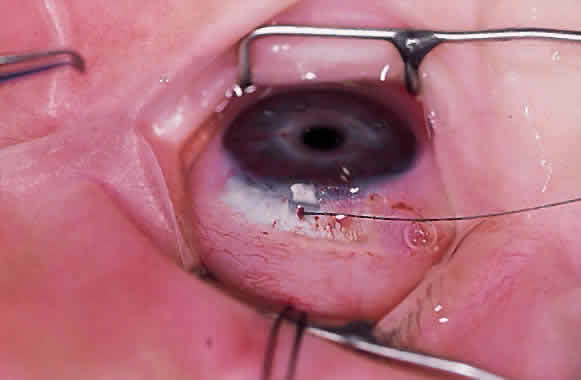

Virtually all of the inhalational anesthetics are known to depress the IOP within minutes of administration.17 Ketamine HCl slowly elevates the IOP as deeper anesthesia is attained.18,19 The benzodiazepines do not appear to have a significant effect on IOP when used in preoperative doses. Midazolam HCl (Versed) is often used as a preoperative sedative in children, and in many cases the child is sufficiently sedated with this medication to perform a quick IOP measurement before the administration of an inhalational general anesthetic. Such a measurement, with the child resting comfortably but not under the influence of the potent inhalational anesthetics, is probably the most accurate. If such a situation cannot be achieved, as in the case of a highly agitated infant or toddler, the anesthesiologist should be aware that it is preferable for the surgeon to measure the IOP as early as possible during the induction of general anesthesia (Fig. 2). At this point in the anesthetic induction, however, airway management is of paramount importance, and the surgeon must defer to the judgment of the anesthesiologist as to when measurements can safely be taken. In most cases, endotracheal intubation is appropriate.

Fundus photography of the optic nerve allows the surgeon to document the extent of progression of the disease (Fig. 4). It is well known that the optic nerve cupping seen in congenital and juvenile glaucoma can to some extent reverse itself,20–22 and this can be used in some cases to gauge the success of therapy. Similarly, axial length measurements by ultrasonic biometry can help establish the degree of disparity between the two eyes, particularly in unilateral cases.23–25 In many cases the disparity decreases after successful therapy,23 and thus a constant or increasing disparity between the two eyes may signal a worsening clinical situation. The Bio-Pen hand-held ultrasonic biometric ruler (see Fig. 2) is a portable device that can be brought to the operating room for intraoperative biometry; because it is similar in size, operation, and appearance to the Tono-Pen, it can also be used in the office setting in young children who have become accustomed to IOP measurements being taken with that device.